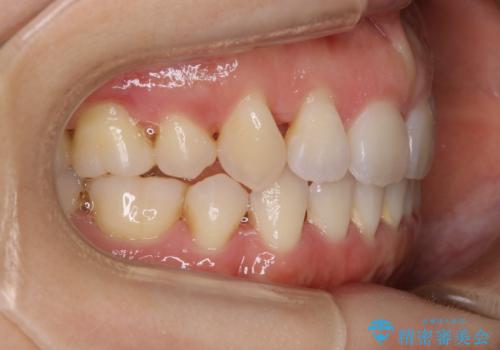

- 前歯のガタつき・噛み合わせの不調を主訴にご来院されました。

患者様のお仕事柄、目立たない装置で矯正したいとのご要望があり、今回はインビザラインを用いて抜歯矯正を行うこととなりました。

本来、抜歯によって得られる大きなスペースのコントロールはワイヤー装置の方が得意とされていますが、こちらの患者様のように犬歯が大きく手前に傾斜していて奥歯の噛み合わせにそれほど問題がないケースではマウスピース装置でも十分にコントロールできることが予測されます。